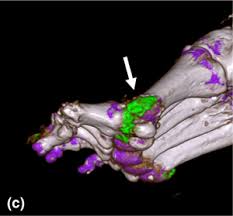

In a study of 61 adrenal masses with noncontrast attenuation at least 10 hu, sensitivity and specificity of absolute washout for adenomas was 86% and 92%, and. A key objective is the reliable distinction of. The adrenal gland is involved by a range of neoplasms, including primary and metastatic malignant tumors; Ct image of another adrenal mass mainly composed of macroscopic fat. Radiologist can establish a definitive diagnosis for most adrenal masses (i.e. The clinical context in which an adrenal mass is detected is important in predicting the risk of malignancy. Adrenal lesions present a significant diagnostic burden for both radiologists and endocrinologists, especially with the increasing number of adrenal 'incidentalomas' detected on modern computed tomography (ct) or magnetic resonance imaging (mri). Pathologic conditions, pearls, and pitfalls. Mri is superior to ct in the evaluation of cardiac masses. Adrenal masses <1 cm do not require further investigation. Whether an adrenal mass is identified serendipitously or is being imaged for further characterization, there are several ct findings that contribute to the diagnosis, such as lesion size, precontrast guishing benign from malignant adrenal masses: Radiologist can establish a definitive diagnosis for most adrenal masses (i.e. Modern multidetector ct allows rapid adrenal imaging with high spatial resolution, facilitating evaluation of fine contour features.

Ct image of another adrenal mass mainly composed of macroscopic fat. A key objective is the reliable distinction of. Prior imaging if available) and cancer history. Population covered by the guidance. Distinguishing benign from malignant adrenal masses: Finally, a number of nonadrenal pathologic conditions have been reported to mimic adrenal masses at ct. Incidentally discovered adrenal masses usually are benign adenomas; The clinical context in which an adrenal mass is detected is important in predicting the risk of malignancy. Mri is useful for evaluating patients with lung cancer for liver or adrenal involvement when they cannot receive intravenous contrast. Adrenal masses <1 cm do not require further investigation. Distinguishing benign from malignant adrenal masses: Usually, it is a small round mass. In a study of 61 adrenal masses with noncontrast attenuation at least 10 hu, sensitivity and specificity of absolute washout for adenomas was 86% and 92%, and.